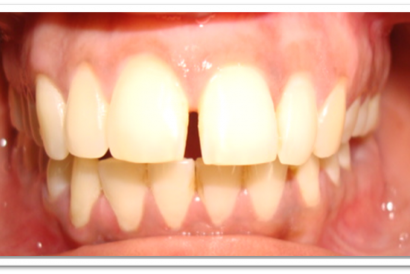

Patient Name:Kevin Haria

Tooth Involved :11 12

Diagnosis :Diastema Between 11 12

Treatment : Diastema Closure Using Nanohybrid Composite

Before